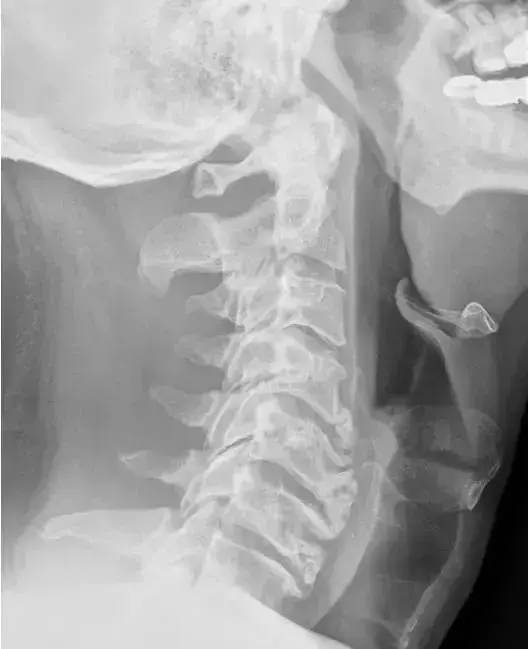

图2、正常的颈椎侧位片

图 6、颈椎生理曲度变直